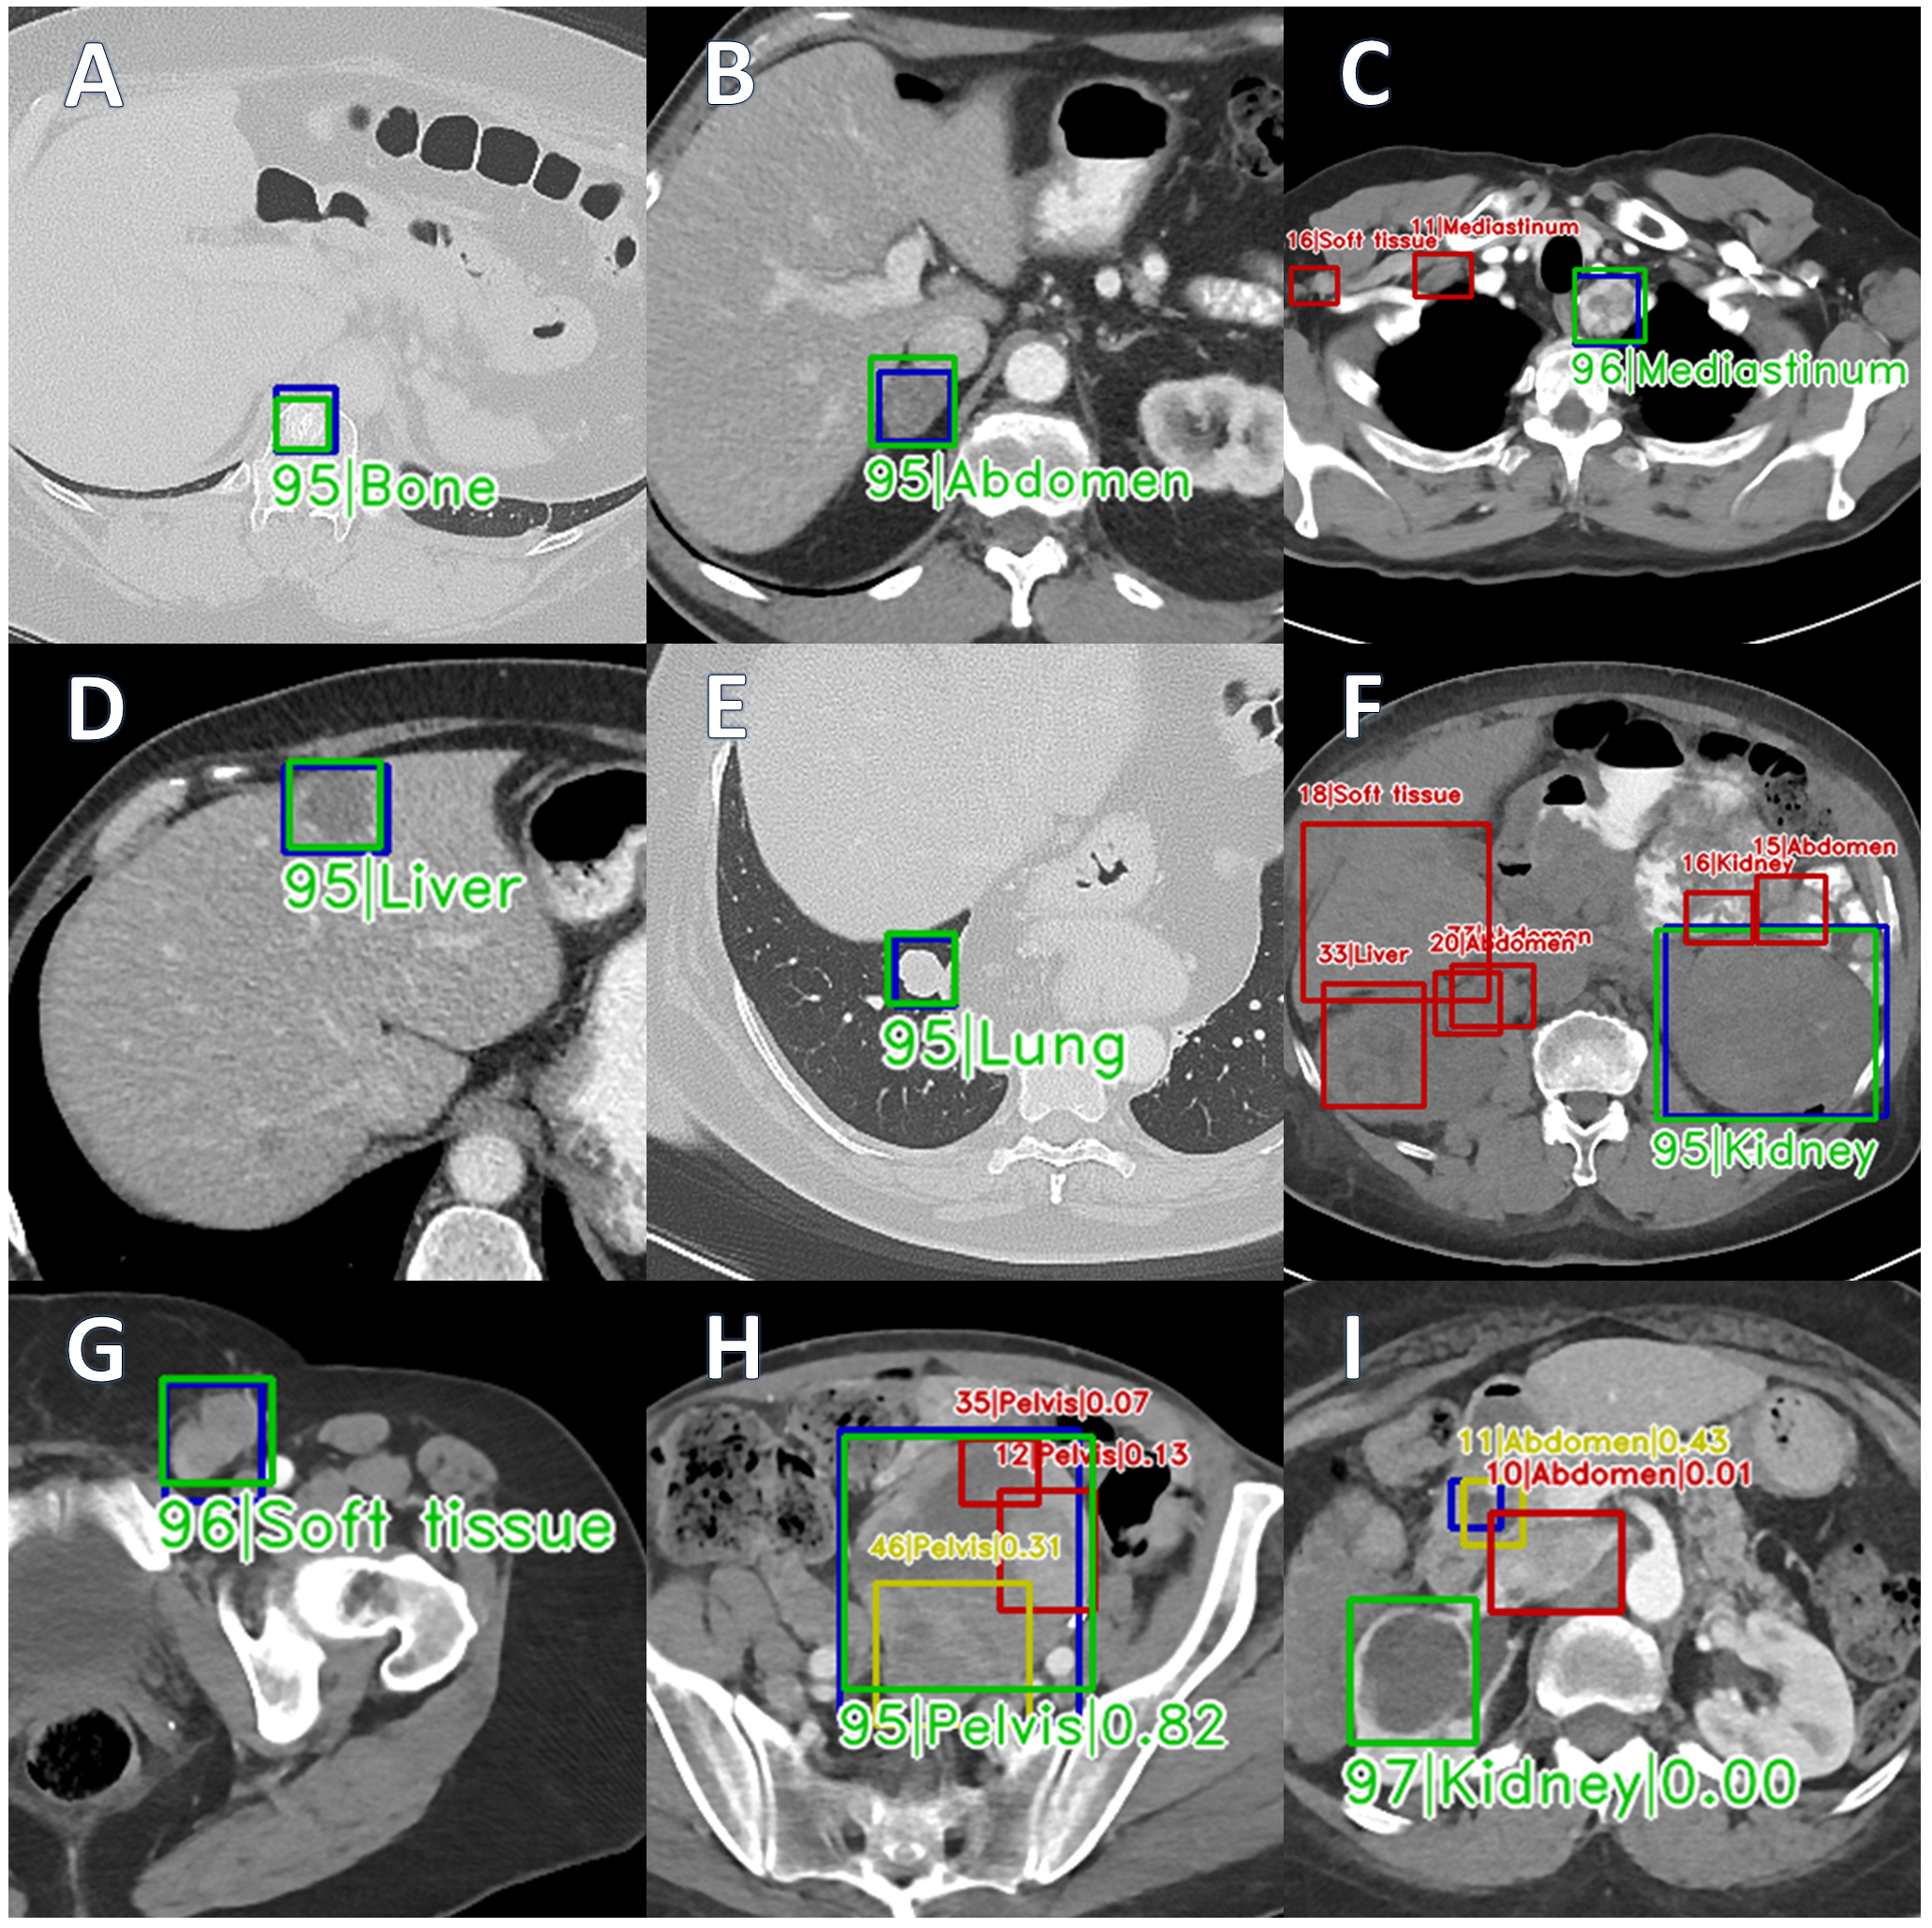

Localizing metastatic lesions is critical for the assessment of tumor burden and lesion status change (growth, shrinkage, unchanged), and it determines the course of patient therapy. Presently, computed tomography (CT) is the preferred modality for imaging patients [1], but lesions in CT can have diverse shapes and appearances with some occurring in standard locations (e.g. liver or lung) while others are rarer (e.g. bone). Radiologists rely on the lesion size as an indicator of malignancy, and size them using RECIST guidelines [1]. However, this guideline varies across institutions due to many factors, such as clinical practice, type of CT scanners, exam protocols, contrast phases used. Presently, automated universal lesion detection (ULD) approaches [2, 3, 4, 5, 6, 7, 8, 9, 10, 11, 12] identify all lesions in a given CT study. ULD with tagging (ULDT) adds diagnostic value by tagging the lesion with the body part in which the lesion is located. Prior work on ULDT [13, 14, 15, 16] used the publicly available DeepLesion dataset [2], but it is incomplete as only clinically significant lesions are annotated while others remain unannotated. It is also severely class-imbalanced [15] with considerable over-representation of certain classes (e.g. liver, lung) over other under-represented classes (e.g. bone, kidney). Moreover, lesion tags are only available for the DeepLesion validation and testing splits (30%).

Dataset. The DeepLesion dataset had 32,735 lesions prospectively annotated with 2D bounding boxes on 32,120 CT slices. Context slices 30 mm above and below the annotated slice were also provided, but they were not annotated. DeepLesion was divided into official training (, 70%), validation (, 15%) and testing (, 15%) splits with the lesions in the validation and testing splits tagged with one of 8 body part labels (bone, abdomen, mediastinum, liver, lung, kidney, soft tissue, pelvis). Patients from were used solely for unsupervised self-training and their annotations (boxes with no tags) were discarded. We used the slice overlap between a fully annotated test set (boxes with no tags) described in prior work[6] and the DeepLesion test set as our final testing set throughout this study. This step provided a near-completely annotated test set with tags mapped from DeepLesion. We then removed the patients in from to ensure no patient-level overlap. Following this, we randomly sampled patients from , and sub-divided them into our final training (70%) and validation (30%) splits. The resultant contained only 11.5% of the total number of lesions in the original DeepLesion dataset. All splits are done at patient level and no patient overlaps exists between , and (see supplementary material Fig. 2 and Table 2 for the construction of these subsets).